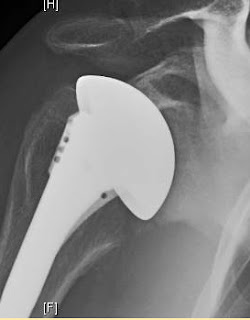

The 6 week postoperative x-ray is shown here. Note that the bone at the glenoid surface as yet to consolidate.